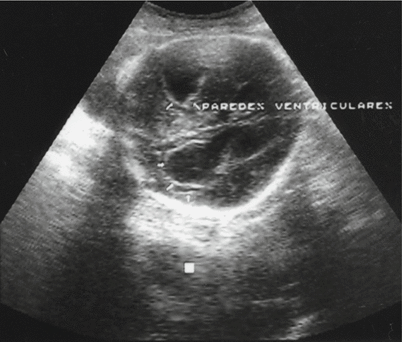

Fig. 15.10

Part of the central nervous system showing dilatation of the lateral ventricles in a case of fetal toxoplasmosis diagnosed by amniotic fluid analysis through polymer chain reaction. Fetal death at 26 weeks of amenorrhea